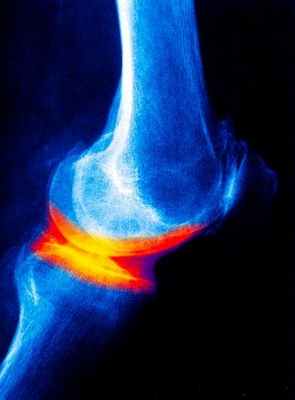

Заподозрить остеоартрозврач-ревматологможет на основании жалоб, истории болезни, осмотра пациента. Для подтверждения диагноза необходимы рентгенограммы наиболее беспокоящих суставов. На снимках видны изменения, характерные для артроза: на ранних стадиях подчеркнут контур костей, образующих сустав, затем сужается суставная щель, образуются костные разрастания по краям сустава.

В зависимости от выраженности изменений на рентгенограммах, различают 4 стадии артроза - от первой, с минимальными изменениями, до четвертой, когда строение сустава практически полностью нарушено. Из дополнительных методов исследования может помочь термографическое (тепловидение) и ультразвуковое (УЗИ) исследование суставов, для выявления воспаления в суставах или окружающих их тканях, чего нельзя увидеть на рентгенограмме.

- 1 стадия характеризуется наличием незначительных морфологических изменений в суставе и проявляется болями при физической нагрузке (рентгенологически будет лишь сужение суставной щели). Морфологические изменения в суставном хряще в1 стадии проявляются появлением шероховатости разволокнения структуры ткани.

- 2 стадия характеризуется постоянными болями в суставах рентгенологически более выражено сужение уставной щели появляются остеофиты морфологически эта стадия характерна появлением бугристости поверхности хряща развитием остеофитов.

- 3 стадия остеоартроза характерна не только болевыми проявлениями, но и появлением нарушений функций суставов. Морфологически 3 стадия проявляется истончением хряща вплоть до исчезновения утолщением внутрисуставных связок резким уменьшением внутрисуставной жидкости

Рентгенологические методы исследования дают, как правило, достаточную информацию о наличии дегенеративных изменениях в суставе. В зависимости от рентгенологической картины проводится и классификация остеоартроза:

- 0 отсутствие рентгенологических признаков остеоартроза

- 1 стадия – кистозная перестройка костной структуры ткани появление маленьких остеофитов признаки линейного остеосклероза

- 2 стадия остеосклероз, более выраженный и появляются признаки сужения суставной щели.

- 3 стадия выраженный остеосклероз остеофиты становятся большими, суставная щель значительно сужается.

- 4 стадия остеофиты более массивные суставная щель практически не визуализируется деформация эпифизов костей их уплощение.

Рентгенологическое исследование суставов.